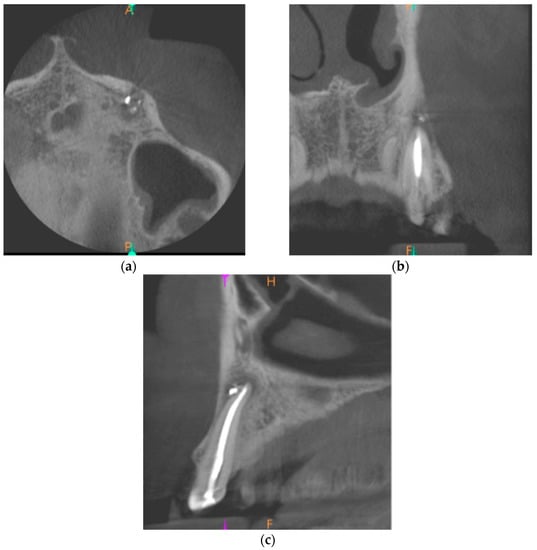

Cone-beam computed tomography (CBCT) was performed. The periapical lesion was measured with the use of CS 3D Imaging v3.5.18 Software (Carestream Health Inc., Trophy, Croissy-Beaubourg, France). The measured dimensions of the lesion were 9.0 × 7.2 × 9.9 mm. The CBCT images of the periapical lesion are presented in Figure 1.

Figure 1. Preoperative cone beam computerized tomography (CBCT) images presenting the periapical lesion around the root of tooth no. 23 (date of CBCT examination: 22 May 2020): (a) axial view; (b) coronal view; and (c) sagittal view.